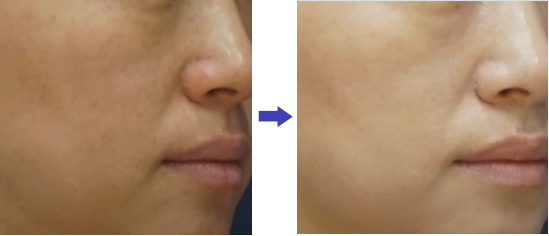

탄력 개선

탄력 개선